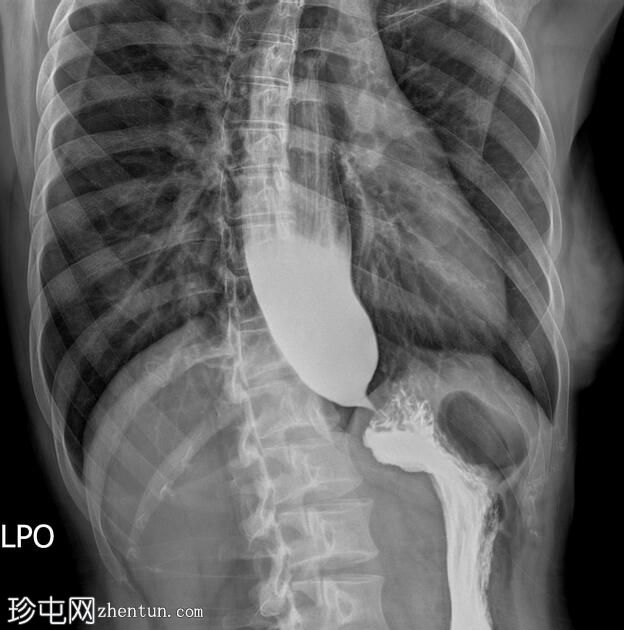

透视检查

斜位

食管扩张,远端平滑狭窄并呈锥形(鸟嘴状),符合贲门失弛症的特征性表现

食管黏膜形态正常,无异常或溃疡

未见食管裂孔疝

钡餐检查显示食管扩张,远端狭窄并呈锥形,形成符合贲门失弛症特征的鸟嘴状外观。